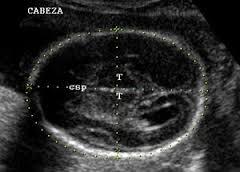

2. 2. Ecografía

2. Cálculo peso: DPB, Perímetro cefálico, Perímetro abdominal, Longitud del fémur